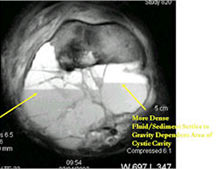

- The cystic spaces filled with hemorrhagic material leads to the presence of fluid-fluid levels on MRIs (so called ABC-like changes or telangiectatic change)

- Fluid-fluid levels secondary to cystic cavities filled with blood products. The sediment from blood products settle to the gravity dependent area of the cavity and the fluid component floats to top thus forming a fluid-fluid level.